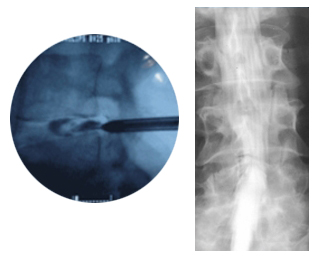

신경차단술

최신영상 진단기를 이용하여 실시간 병변부위를 관찰하고 척추 내에 약물주입하여 척추관절의 경막외 차단술, 추간 관절 신경차단술, 척추 신경근 차단수르 교감신경절 차단술을 시행하고 있습니다.